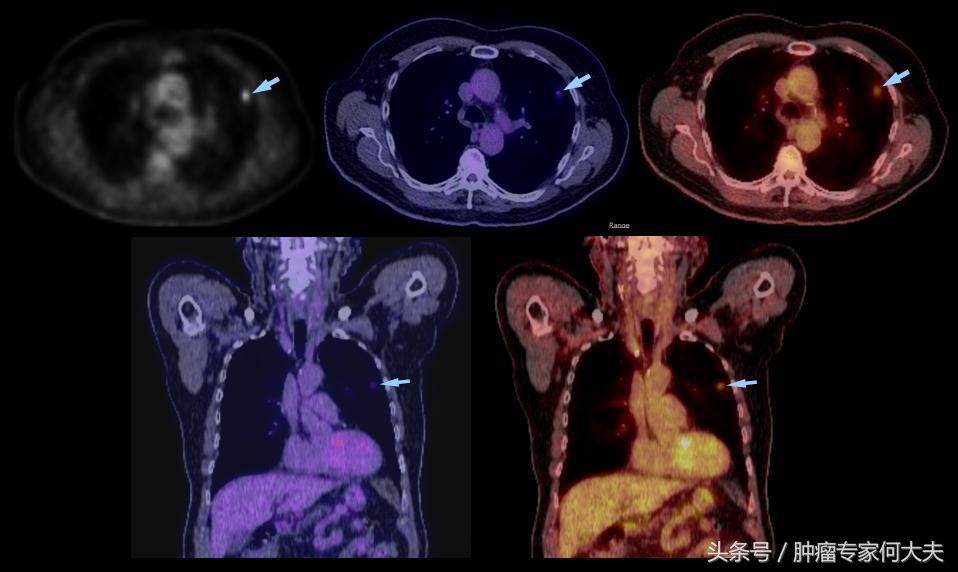

肺影像学

在第二年接近第三年的那次复查中,小豆被医生告知右肺也长了瘤子,医生建议小豆穿刺活检,小豆还是比较配合的,做了肺穿刺活检术,术后病理结果证实也是肺腺癌,和以前病理结果一样,医生推测可能是转移,并对取下的组织进行了基因检测,仍然没有检测到敏感突变基因,但医生建议小豆可以尝试口服“易瑞沙”,因为在生病的2年多时间里,小豆研读了很多肺癌的专业书籍,对肺癌的知识了解甚多,因此她同意了口服靶向药,在口服靶向药的两个月里,除过面部皮疹,没有其他不良反应,但用药三个月后,复查肺部CT,病灶依然没有明显变小迹象。医生考虑无效,于是就把靶向药停了。没有任何治疗,她还能撑多久?她自己不知道,医生们也众说纷纭,反正总体是时间不会太久,有的医生说也就半年一年左右,小豆说当时自己想“反正都这样了,与天争命也无济于事,静静等待未来会发生什么”。

肺相关淋巴

就这样,读书、看报、上网,有时候和朋友出去游游逛逛,虽然癌症在身,她不能积极作为,只能听天由命,但是半年过去了,右肺出现的病灶生长势头不明显,一年过去了,两年过去了,三年过去了,一直在复查,但是复查的结果总是说变化不显著。但医生仔细对比三年之初与三年之末(最近)的片子,瘤子是有所长大,但都长的不算多,个别小病灶甚至自然变小。 最近,小豆说自己喘的明显了,夜里咳嗽厉害,难以成眠,要来查查,我给做了胸部CT检查,结果提示两肺多发占位病变,对比了她3年前刚发现右肺时的片子,这次明显变大,目前尚未做出诊疗计划。但针对小豆这样的病人,实属少见。人类针对肿瘤的认识仍然处于很原始的阶段。就拿肺癌来说,现代医学研究算是比较成功的一种瘤种,已经认识到一部分肺癌患者因为存在某些基因突变可以从治疗中获益,但是没有突变的患者并不是一定就很危险,个体差异相当大。希望每个人不要因为得了肿瘤,就自暴自弃。